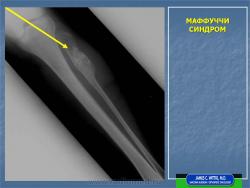

Одновременно с появлением кожных сосудистых опухолей у больных развиваются плотные узлы энхондром, растущие из костей, особенно из пальцев кистей и стоп и метафизов длинных трубчатых костей верхних и нижних конечностей. Они прогрессируют до окончания роста костей, что ведет к переломам, развитию контрактур и резких деформаций. Отмечаются неврологические симптомы.

Энхондроматоз (МКБ–10: Q78.4 Энхондроматоз, OMIM 166000, R) наследственный дефект энхондрального остеогенеза, при котором хрящ не рассасывается и не замещается костной тканью (продолжает расти по мере роста организма, тогда как в норме оссификация наступает на 3-4-м мес. эмбрионального развития). Может поражаться любая кость вторичного окостенения, в длинных костях обычно локализуется в метафизах (у детей) и может быть в диафизах (у подростков и взрослых). Наиболее часто поражаются большеберцовые, бедренные и плечевые кости, мелкие кости кистей и стоп, кости таза, реже рёбра, грудина, кости черепа. Заболевание проявляется при рождении или в раннем детском возрасте.

Клиническая картина. Заболевание выявляется в раннем детском возрасте, с началом ходьбы появляются деформации костей, хромота, прогрессирующее укорочение конечностей. Нередко первым проявлением болезни служат патологические переломы измененной кости; гемангиомы (при синдроме Мафуччи). Рентгенологически трубчатые кости умеренно или значительно укорочены, эпиметафизы булавовидно расширены, вздуты; в метафизах определяются очаги просветления неоднородной структуры.

Макроскопически отмечают бесформенные бугристые образования гиалинового хряща, разделённого на дольки, иногда с участками обызвествления или окостенения; деформация костей в виде искривления и укорочения.

Рисунок 2.6